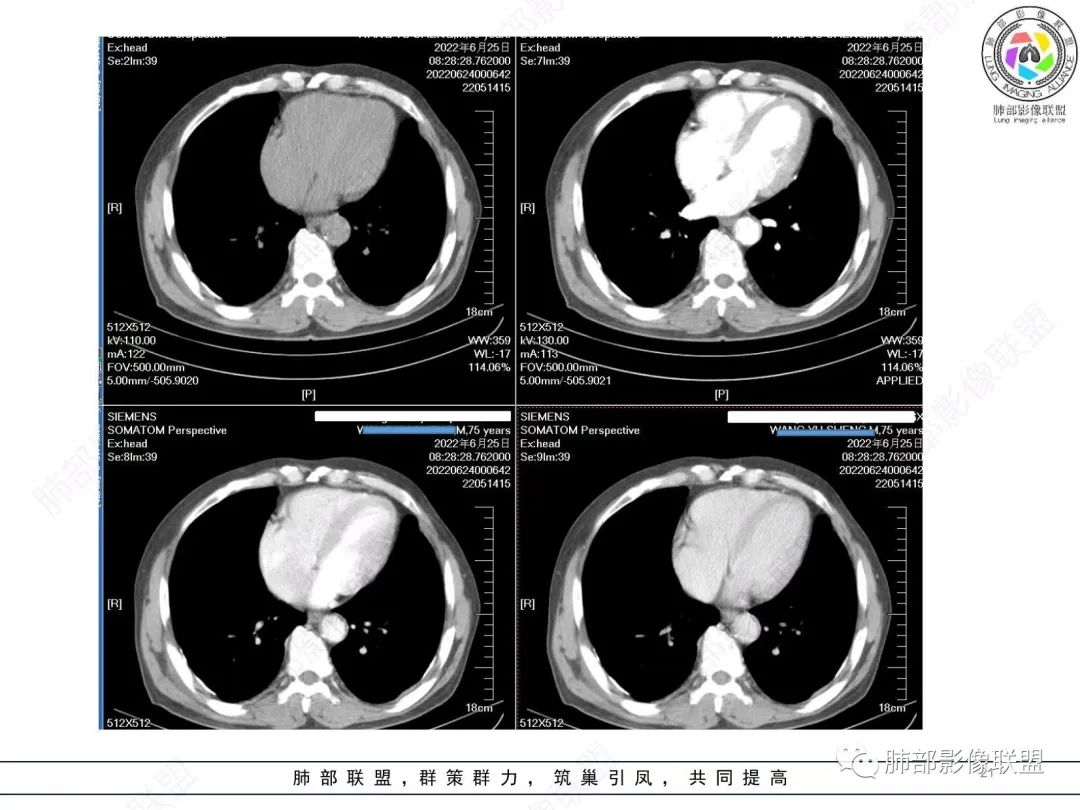

原发性肺肉瘤样癌(PSC)一组临床罕见的肺部肿瘤,属于上皮细胞源性肿瘤,仅占肺部恶性肿瘤的0.3%~4.7%。为含有肉瘤形态细胞或肉瘤样分化的非小细胞肺癌,癌成分多为鳞癌或腺癌,肉瘤成分最常见的是纤维肉瘤。

肺肉瘤样癌的CT表现主要特点:

1)部位:周围型或中央型软组织肿块,以周围型为多见,且肿瘤多位于肺上叶。如本例:该肿瘤位于左肺上叶。

2)大小及形态:由于本病恶性程度高,早期症状不明显,发现时肿块均较大。如本例病变巨大。

3)肿块边界和边缘:多较清楚,呈圆形、类圆形,且由于肿块生长速度不均匀,可见分叶,毛刺少见。有报道肿块周围毛玻璃影是多形性癌特征表现。

4)密度:肿块平扫为软组织密度,由于体积较大,内部常见大片状坏死,可出现不规则厚壁空洞或坏死内多发无壁小空洞,坏死多不均匀:坏死灶内可见如柳絮样的斑片样强化灶,坏死边缘与非坏死区分界不清本例坏死较明显,密度不均匀。

5)肿瘤强化方式:肺部恶性肿瘤强化程度与其血供丰富程度相关,血供丰富多强化明显,反之则较差。由于PSC 周边实性部分富血供及内部黏液变性、坏死,增强后肿块多数呈轻-中度边缘环形强化或不均匀小斑片状强化。国外学者对照病理发现肿瘤细胞或胶原组织增强扫描时强化,无强化的低密度区代表了黏液样变性区和出血坏死区。